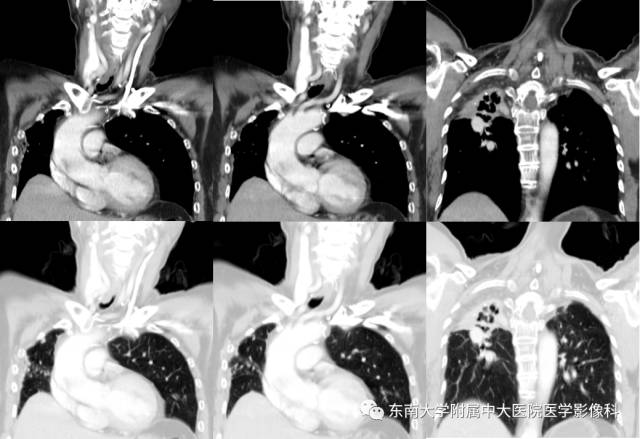

病例2

女,65岁,因“气喘、气促半年余”入院。

CT

增强